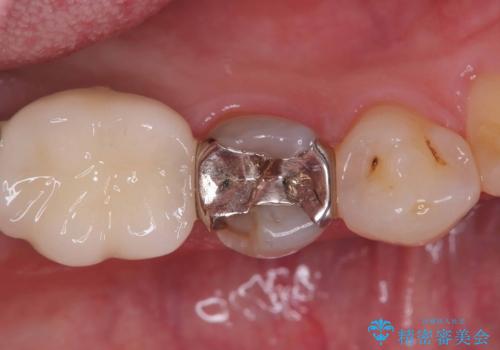

- 「食事をしていたら歯が欠けた」を主訴に来院された患者様です。

メタルインレーが入っており、インレーとの境の歯質が欠けている状態でした。

不幸中の幸いで欠けているところが根っこよりも上だったため、オールセラミッククラウンで治療を行いました。

銀歯を除去後、やはり銀歯の下は虫歯になっていましたので、虫歯を除去した後にオールセラミッククラウンで被せました。